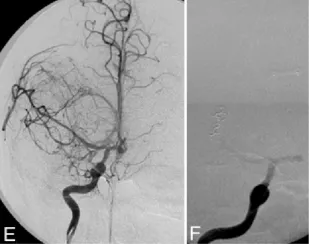

图3. 上:病理切片(H&E染色,×30)显示肿瘤细胞密集,呈上皮样与梭形细胞双向分化,束状排列;下:S100蛋白免疫组化染色(×200)呈弥漫阳性。